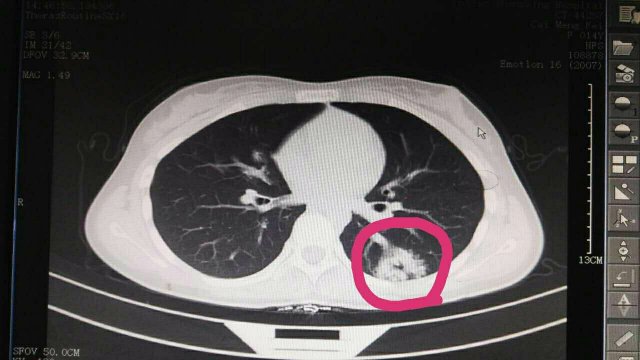

蔡**,女,14歲因“反覆頭暈3年余”,求診莆田及莆田各三級(jí)醫(yī)院,做過很多輔助檢查,均未確診,于2017-2-26日就診我院門診,接診是我院兒科林富醫(yī)師,經(jīng)過認(rèn)真仔細(xì)查體,發(fā)現(xiàn)患兒左側(cè)肩胛骨可聞及Ⅱ-Ⅲ/Ⅵ級(jí)收縮期雜音,為明確診斷,即刻請(qǐng)我院莊姞副主任醫(yī)師(原莆田市Di一醫(yī)院NICU主任)會(huì)診,查胸部CT發(fā)現(xiàn)左肺下葉背段血管畸形。莊姞副主任醫(yī)師告訴我們,部分型肺血管畸形如果不認(rèn)真查體是很難查體的到,年輕醫(yī)師能如此仔細(xì)查體,確診多家醫(yī)院未確診的疾病,不得不對(duì)林醫(yī)生豎起大拇指,通過此次經(jīng)歷,可見臨床醫(yī)生必須熟練掌握臨床三基的重要性。